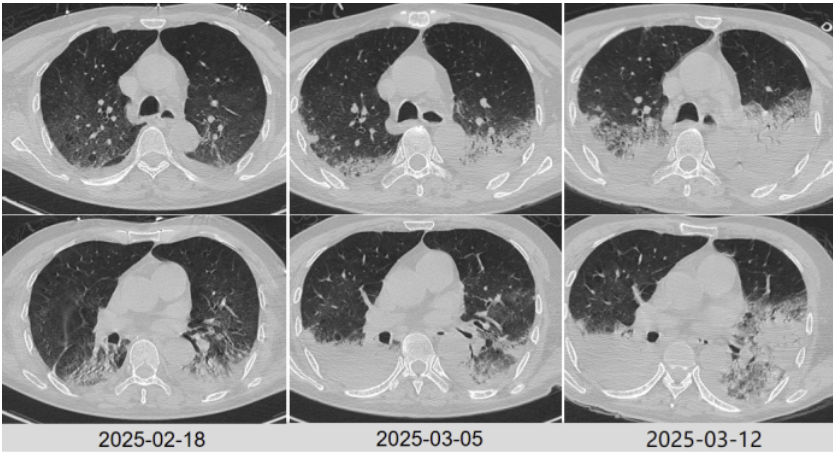

治疗后患者体温逐步恢复正常,炎症指标下降。复查胸部CT(2025-02-18)可见双肺炎症稍吸收(图3)。

图3 患者治疗前后胸部CT对比

2025年3月5日复查胸部CT病灶较前进展(图4),炎症指标有所回弹,以中性粒细胞升高为主,抗感染方案调整为哌拉西林他唑巴坦4.5 g q9h+奥马环素300 mg qd po。

图4 患者复查胸部CT对比

2025年3月12日患者氧合无明显改善,复查胸部CT示肺部病灶进展(图4)。将抗生素方案调整为美罗培南+米卡芬净+莫西沙星,甲泼尼龙抗炎,无创呼吸机辅助通气。